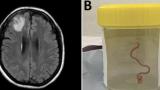

Gölet ve nehirlerde yaşayan solucan, şizofreni tedavisinde kullanılabilir